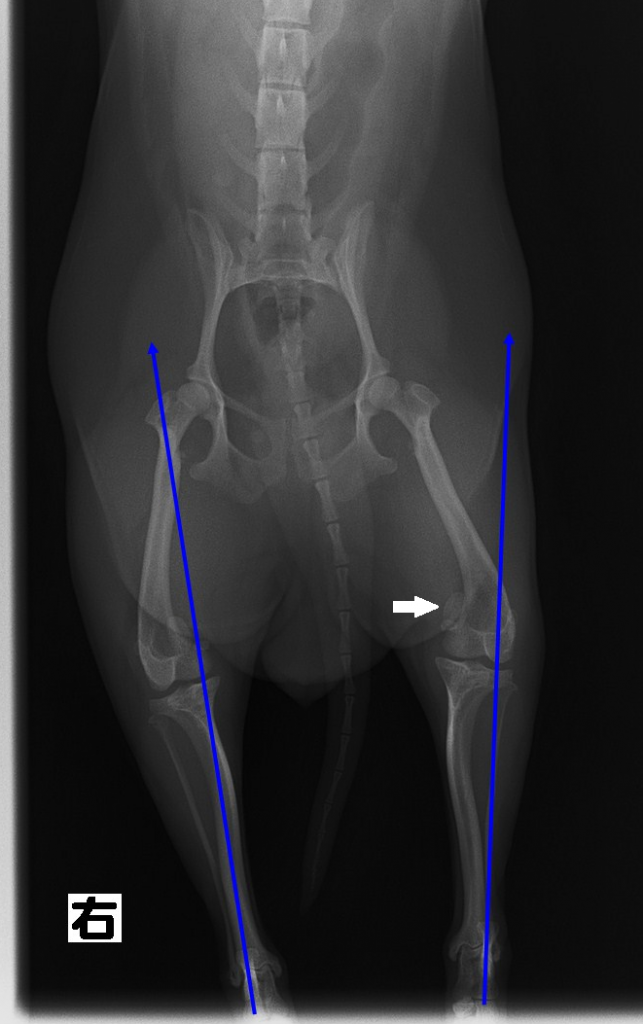

さて、膝蓋骨の脱臼とはどのようなものか?画像を見て説明します。

写真は下半身を正面から撮影したレントゲン写真です。白い矢印(⇨)で指した楕円形の骨が『膝蓋骨』です。本来の位置からは外れてしまっています。またカカトからヒザまでのスネの骨が真っ直ぐ伸びておらず内側へ曲がってしまっています。正しく言うと内転といって骨が内回りに捻じれてしまっています。このような骨格の犬は脱臼しやすいといえるでしょう。

上の画像は脱臼の手術2ヶ月後の写真です。矢印(⇨)が膝のお皿(膝蓋骨)です。正しい位置に戻っています。